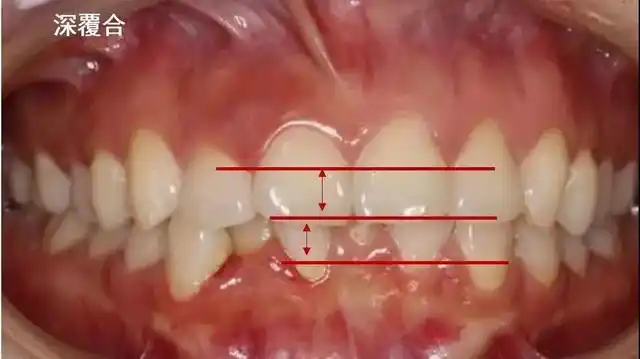

很明显上排牙完全把下排牙包住了,这就是传说中的"深覆合"吗?

也就是说,如果 上牙包住下牙的范围超过了2~3mm,就是深覆合.